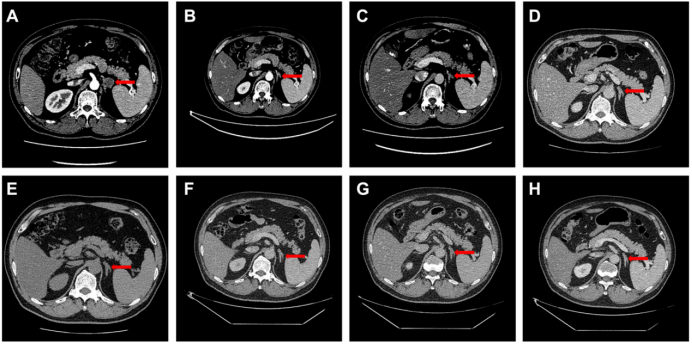

手术2个月CT显示肾上腺有一个2厘米大小的转移性肿瘤(图A),表明疾病进展,尽管PD-L1为阴性,但由于TMB-H且EGFR / ALK突变阴性。患者于2018年10月开始接受nivolumab治疗(240毫克)。在15个疗程后,患者获得了完全缓解(CR),左肾上腺转移性肿瘤明显消退(图B–E)。在第16个疗程之后,患者咳嗽伴轻度呼吸困难,胸部CT显示小叶间间隔增厚和胸膜下玻璃样混浊。Nivolumab治疗中断3个月,但症状恶化,通过乙酰半胱氨酸和皮质类固醇治疗3个月,症状消失。停药后第4、8和12个月,没有进展。在治疗后随访的20个月内(至2020年5月),患者未见复发或转移。